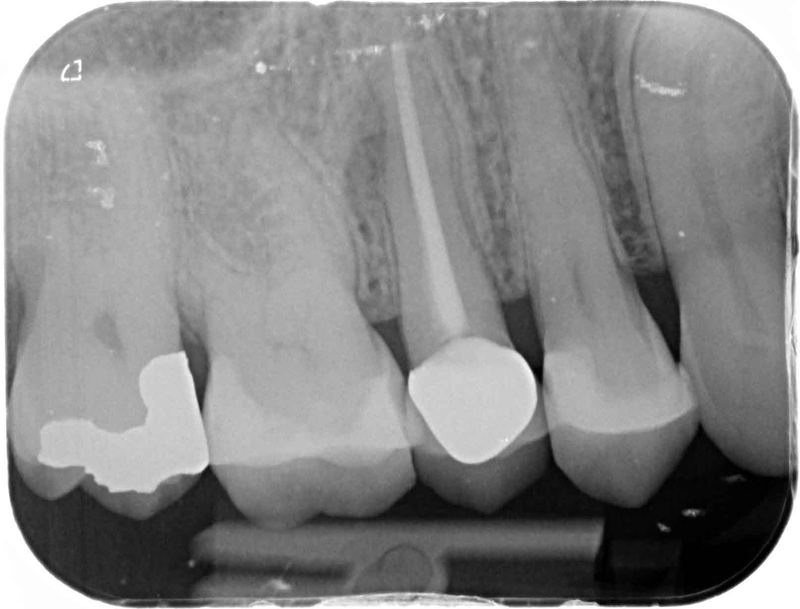

Case 24 – Endodontics

Transillumination after trauma